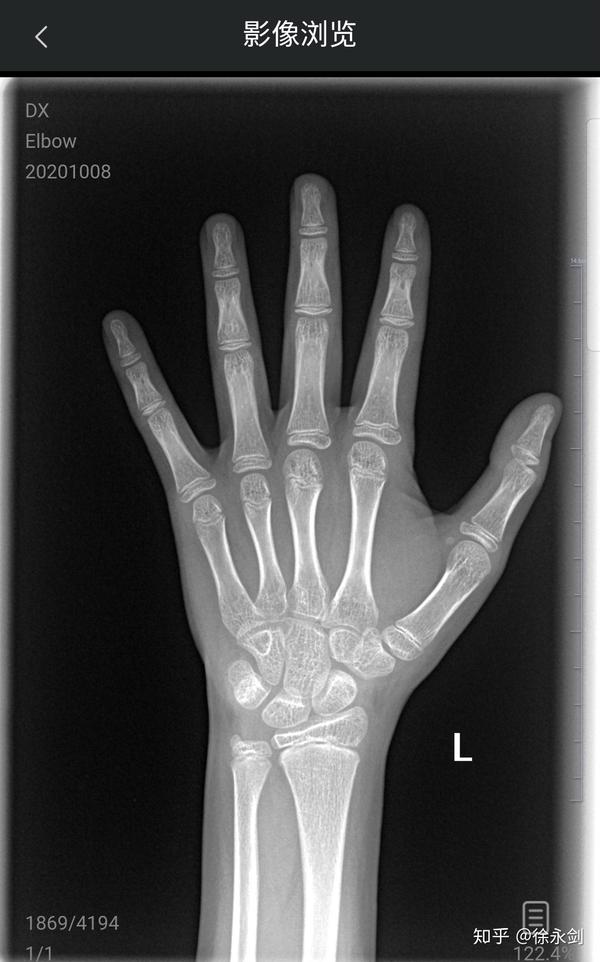

15岁左手骨龄,还能长高吗?

大家能帮我看一下骨龄吗,现在我15岁身高172想知道还能长多少